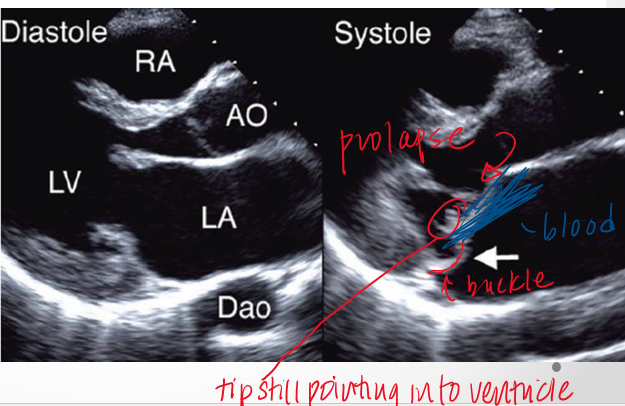

how do the leaflets bulge in mitral valve prolapse?

upward and back into left atrium but tips still point into LV

what is flail mitral leaflet?

when there is chordal rupture

describe flail vs prolapse?

in prolapse chordal connections of leaflet to pap muscle are still intact so tip will still point to LV apex

in flail tip of leaflet will point towards the roof of the LA in systole